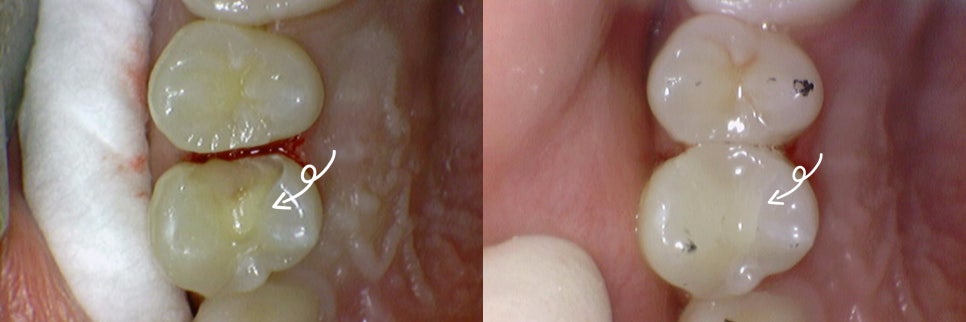

다음으로는, 신경치료를 진행한

치아 앞에 있던 작은 어금니의 인레이 과정입니다.

마찬가지로 충치 제거 후

치아의 뒷면에서 교합면으로 이어지는 형태의

(Distal – Occlusal, DO) 와동을 형성하여

인레이를 올릴 수 있는 모양으로

만드는 것이 필요합니다.